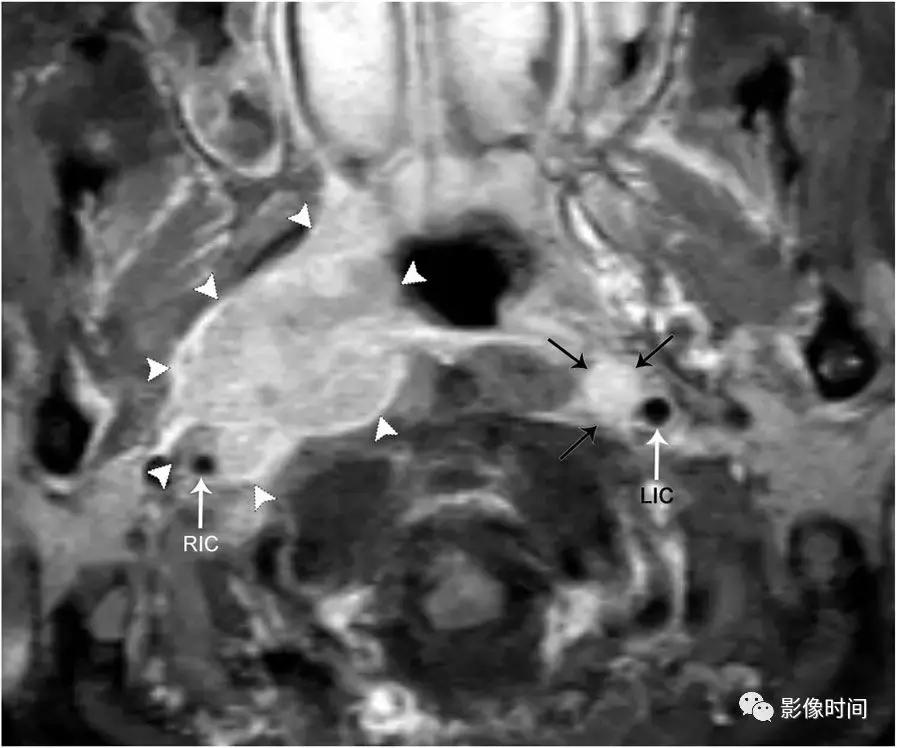

轴位 T1WI+C 显示不均匀强化肿块,完全包裹左侧颈内 (LIC) 和颈外动脉 (LEC)。注意左侧颈内动脉的管腔与右侧颈内动脉 (RIC) 的管径一致。

轴位 T1WI+C 显示鳞状细胞癌直接侵犯到颈动脉间隙。与左颈内动脉(LIC)相比,右颈内动脉(RIC)被包裹、变窄和横向移位。还有一个左侧咽后淋巴结 (黑色箭头)。